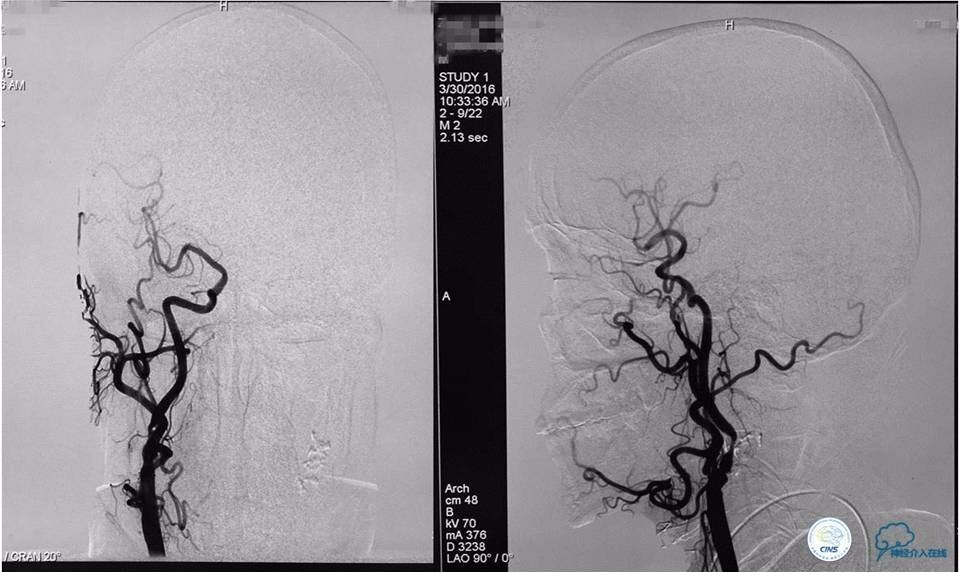

入院后造影检查:

右侧椎动脉正(a)、侧(b)位造影显示右侧椎动脉V4段重度狭窄及右侧椎动脉V4段动脉瘤,狭窄位于瘤颈处,狭窄率为70%,动脉瘤大小为6.99mm×5.95mm,瘤颈宽为3.58mm。